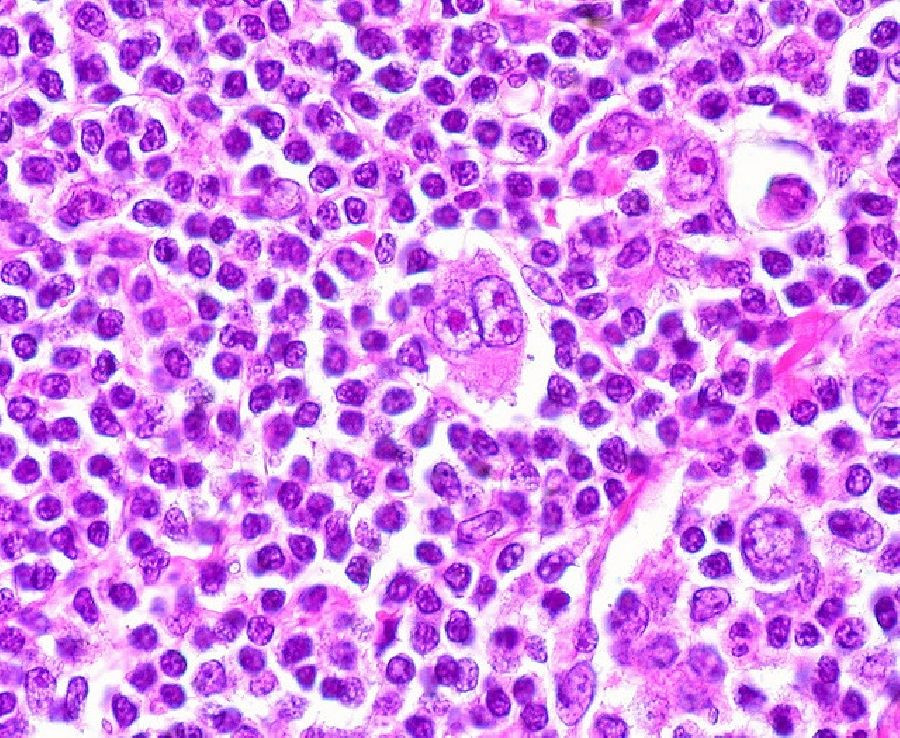

El linfoma no Hodgkin (LNH) es un grupo de cánceres que se originan en los ganglios linfáticos y afectan los glóbulos blancos del sistema inmunitario llamados células B, que crecen sin control y crean tumores en los ganglios linfáticos, el bazo u otros tejidos.

Un equipo de investigadores dirigido por Elisa Oricchio, investigadora de la EPFL, en Suiza, ha identificado uno de los mecanismos utilizados por el NHL para secuestrar el sistema inmune. Los científicos han descubierto que ciertos pacientes con LNH tienen una forma mutada y sobreactivada de una proteína llamada catepsina S, responsable de cortar otras proteínas en pequeños fragmentos que luego se exponen en la superficie de las células tumorales. Estos fragmentos median las comunicaciones entre el cáncer y las células inmunes.

"Cuando la catepsina S está activa, las células cancerosas interactúan con las células inmunes llamadas células T CD4 +, que ayudan al crecimiento del tumor, mientras mantienen la distancia social con las células T CD8 +, que atacarían y matarían el tumor", explica Elie Dheilly, una de los autores principales del estudio.